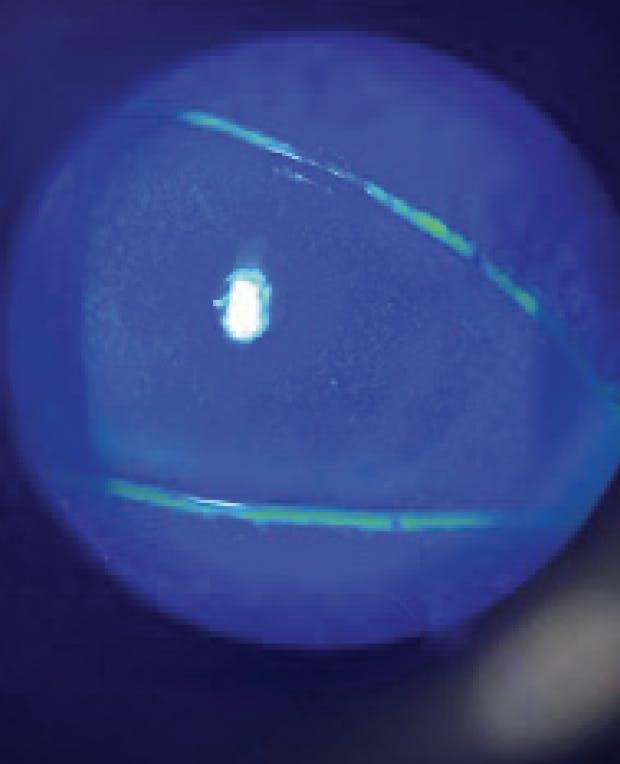

A 70-year-old patient presented to our practice for cataract evaluation due to decreased vision OS>OD. During the consultation, superficial punctate keratitis (SPK) OS was observed, and the cataract surgeon referred him internally to my dry eye clinic for further evaluation. Corneal staining showed 3+ SPK OS and punctate erosions, and clinical examination revealed MGD 2+ OU (Figure 1). The patient was using Lotemax and artificial tears. His VA was 20/25 OD and 20/70 OS. During the interview, the patient said he had been wearing monovision contact lenses for more than 35 years. He subsequently revealed that he had been prescribed various treatments for dry eye by another optometrist, including multiple doses of steroids and different dry eye drops, all with no discernible effect. Corneal sensitivity was tested with a cotton swab, revealing decreased corneal sensitivity in all but the superior quadrant.

Based on the totality of the clinical evidence, the patient was diagnosed with NK, likely secondary to his long duration of contact lens wearing. The patient was started on Oxervate (Dompé) 6 times per day for 8 weeks. VA was 20/20 OS after the treatment and repeat corneal staining suggested a healthy cornea (Figure 2).